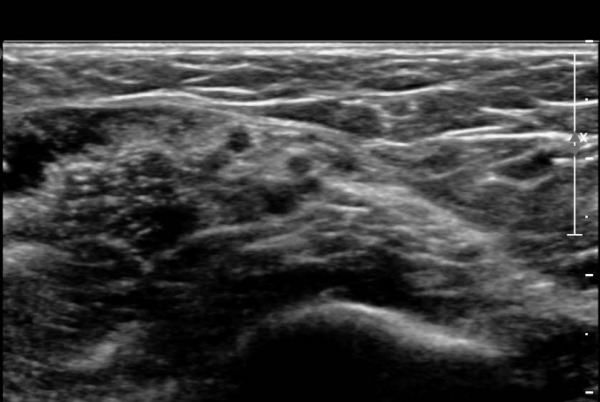

ŽÃËÀÚ¸¦ »ó¹ÚºÎ ¸»´ÜÀ¸·Î  ¿Å°Ü ÆÈ²ÞÄ¡ ºÎÅÍ ±ÙÀ§ºÎ·Î À̵¿ Çϸ鼭 Á¤Á߽Űæ Ⱦ´Ü¸é°Ë»ç¸¦

½ÃÇàÇÏ¿´´Ù(»çÁø 2).  ÆÈ²ÞÄ¡ ÁÖ¸§  ¾à  3cm ±ÙÀ§ºÎ¿¡¼­ Á¤Á߽ŰæÀÇ ÀϺΠ´Ù¹ß(fascicle)ÀÇ Àú¿¡ÄÚ ºÎÁ¾ÀÌ

°üÂûµÈ´Ù(»çÁø 3 , 4,  5,).